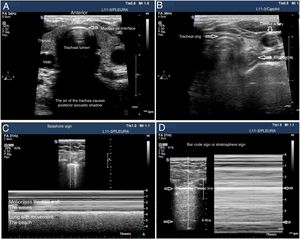

The tracheal ultrasound has proven to be non-inferior to capnography to rule out esophageal intubation.17 For this purpose, it is necessary to use a linear or convex transducer and acquire the cross-sectional view from the anterior region of the neck, in the mid-line above the sternal notch. In this plane, the trachea looks like a hyperechogenic inverted U-shaped line generated by the mucosa-air interface and a posterior comet-tail artifact (Fig. 1A). The correct intubation of the trachea does not cause any changes in the image described since no new interface between the patient’s airway and the OTT is generated (both contain air). Also, because the OTT is located behind the artifact generated by the trachea (which would limit its visualization). On the echocardiography, the accidental intubation of the esophagus generates a new interface between the esophageal mucosa and the air inside the OTT giving rise to a second comet-tail artifact that originates at the deepest level of the trachea and is lateral to it (Fig. 1B). The main advantage of this type of study is that ventilation does not need to be started to detect the incorrect position of the OTT, thus avoiding the possibility of aspiration of gastric content; its limitations are the impossibility to see the OTT directly from inside the airway and the patient’s possible anatomical alterations.

Utility of the tracheal and pleural ultrasound for OTI verification purposes. A) Tracheal ultrasound image showing the trachea with its posterior acoustic shadow surrounded by the thyroid. B) Tracheal ultrasound image with the transducer displaced towards the neck left region. The arrow points at the esophagous. C) Pleural ultrasound image with normal airing pattern indicative that the lung is insuflated. D) Pleural ultrasound image with bar code sign indicative that the lung is not insuflated. Possible contralateral selective intubation.

Pleural ultrasonography provides direct anatomical information on the expansion of the lungs and entry of air into the lungs.18 It can replace auscultation and chest x-rays as the method to rule out accidental selective bronchial intubation (ASBI). For this purpose, it is required to use a linear or convex probe to examine, at least, the upper and lower points of the BLUE protocol in both hemithoraces.19 In these planes, on the 2D ultrasound, the pleura appears as a horizontal hyperechogenic line with movement generated by the slide of the parietal pleural surface over the visceral pleura with respiratory movements called lung sliding or lung displacement sign.20 On M-mode it can also be registered statically by cutting the pleural line producing an image called seashore sign. The presence of both signs in each hemithorax is indicative of bipulmonary insufflation (Fig. 1C). The consequence of ASBI is the lack of airing of the contralateral lung that can be found by the absence of lung sliding and a typical «bar code» pattern or stratosphere sign on M-mode (Fig. 1D). The transformation of a unilateral bar code pattern into a normal lung sliding pattern associated with the partial removal of the OTT is indicative that the initial position of the tube corresponds to an ASBI of contralateral lung (Fig. 7). The main advantages of this kind of examination are the possibility of showing the airing of the lung without having to use the stethoscope and its immediacy compared to the chest x-ray. The main limitation is the existence of differential diagnoses of the stratosphere sign (lack of ventilation, pneumothorax, tumors, etc.).